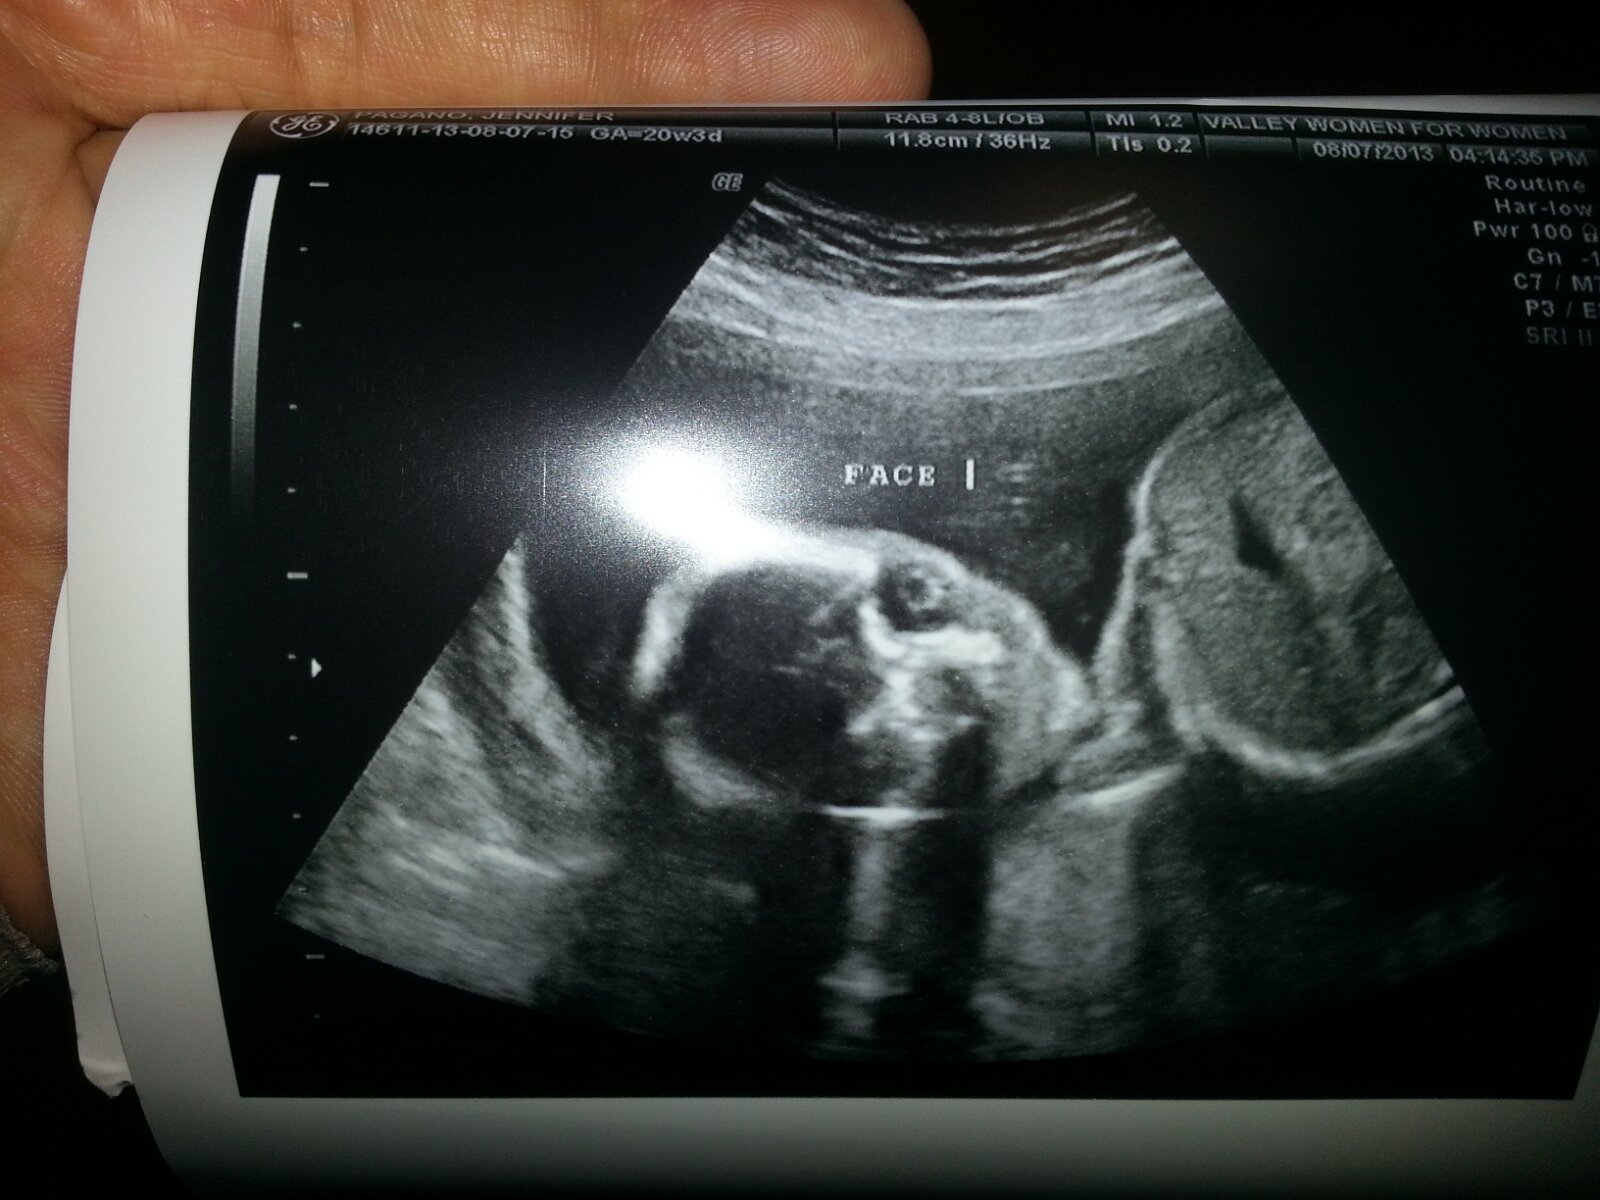

Our Baby

2013-08-07

August 7th